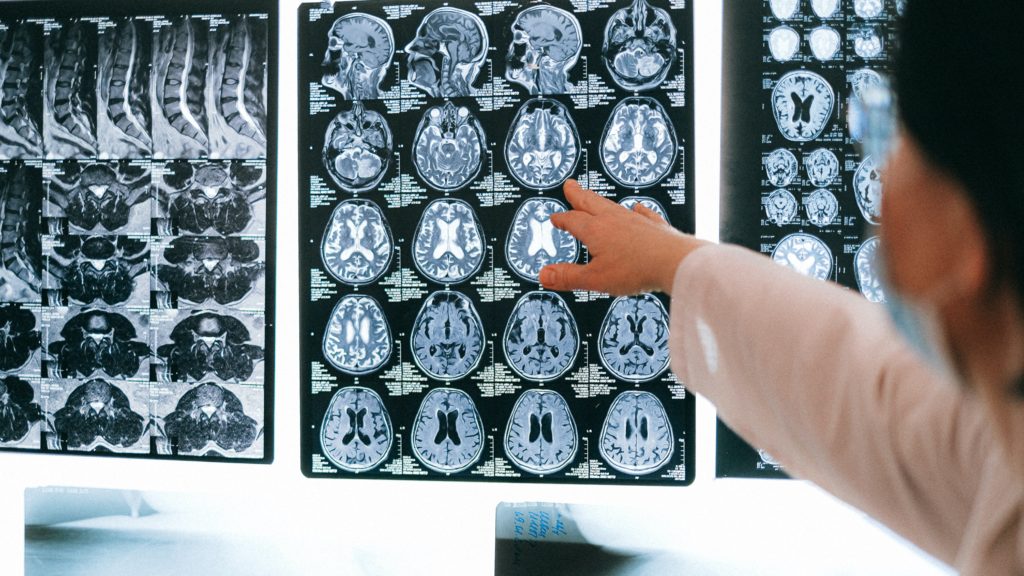

Mindkét kutatáshoz agyi felvételeket használtak fel csapatával, előbbihez értelemszerűen pszichopata gyilkosok agyáról készült képeket, utóbbihoz a kórban szenvedők agyáról készítettek felvételeket. Természetesen szükség volt kontrollcsoportra is, és többek között Fallon is vállalkozott a feladatra. Akkor még nem is sejtette, hogy milyen döbbenetes felfedést tesz majd: miközben az Alzheimer-kutatáshoz használt anonimizált felvételeket nézegette, az egyik alanynál észrevette a pszichopátiára jellemző jeleket. Mint kiderült, az ominózus képen az ő agya látható.

Képünk csak illusztráció (Fotó: Anna Shvets/Pexels)